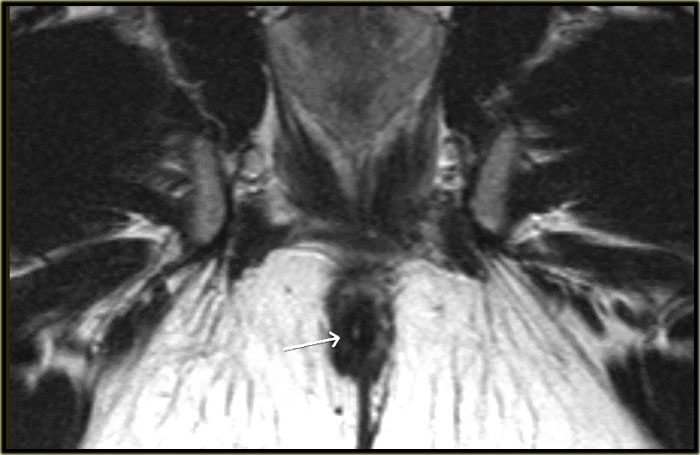

Rò xuyên cơ thắt

Bên trái là hình ảnh cắt ngang chuỗi xung T2W và T2W kết hợp xóa mỡ của một đường rò xuyên cơ thắt.

Khuyết hổng qua cơ thắt trong và cơ thắt ngoài ở vị trí 6 giờ hiện rõ và nổi bật hơn trên hình ảnh xóa mỡ.

Bên trái là hình ảnh cắt ngang chuỗi xung T2W xóa mỡ của một đường rò xuyên cơ thắt với lỗ mở niêm mạc ở vị trí 11 giờ.